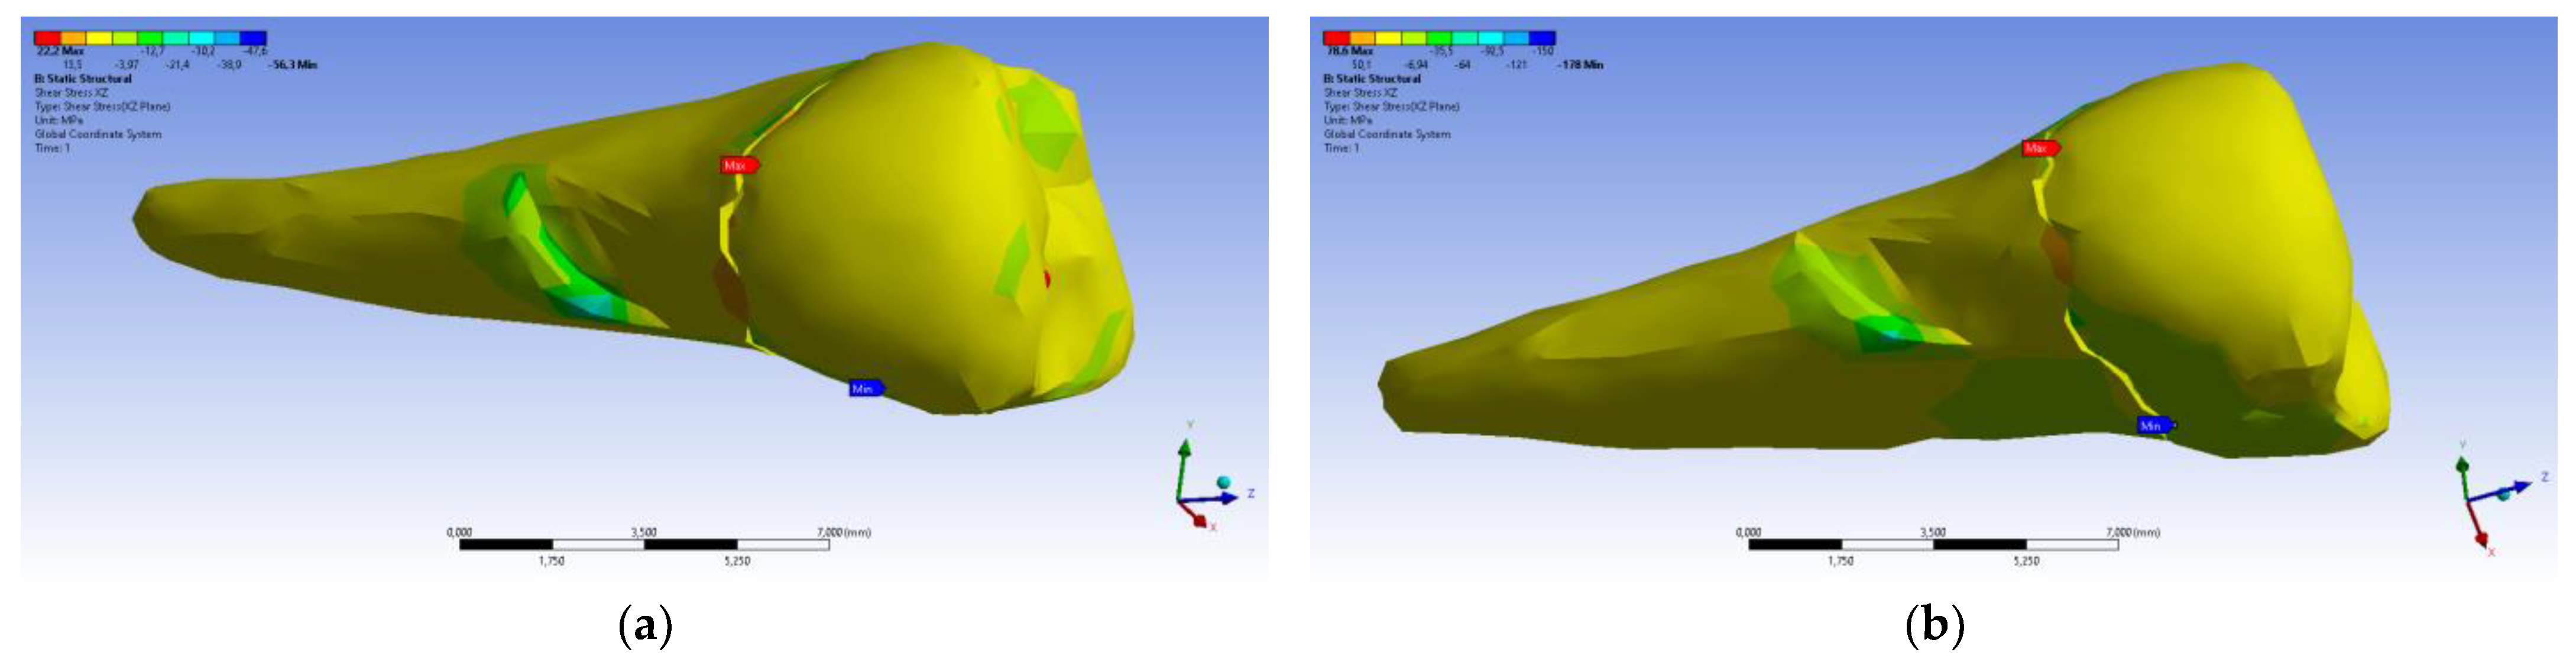

3. Finite Element Analysis (FEA) of Mandibular Right Premolars

| Total Deformation | Deformation in X Direction | Deformation in Y Direction | Deformation in Z Direction | Equivalent Stress | Normal Stress X | Normal Stress Y | Normal Stress Z | Maximum Main Stress | Minimum Main Stress | Tangential Stress XY | Tangential Stress YZ | Tangential Stress XZ | |

|---|---|---|---|---|---|---|---|---|---|---|---|---|---|

| Minimum | 0 mm | −4.24 × 10−3 mm | −2.52 × 10−2 mm | −1.56 × 10−2 mm | 1.01 × 10−6 MPa | −35.6 MPa | −57.1 MPa | −104 MPa | −15.2 MPa | −152 MPa | −43.7 MPa | −39.6 MPa | −56.3 MPa |

| Maximum | 2.77 × 10−2 mm | 3.57 × 10−3 mm | 6.98 × 10−4 mm | 4.78 × 10−3 mm | 248 MPa | 61.5 MPa | 177 MPa | 72.2 MPa | 195 MPa | 21.4 MPa | 44.2 MPa | 117 MPa | 22.2 MPa |

| Minim. in | Cementum | Cementum | Enamel | Enamel | Cementum | Cementum | Enamel | Enamel | Enamel | Cementum | Enamel | Enamel | Cementum |

| Maxim. in | Enamel | Enamel | Cementum | Enamel | Cementum | Enamel | Enamel | Enamel | Enamel | Enamel | Cementum | Cementum | Cementum |

| Total Deformation | Deformation in X Direction | Deformation in Y Direction | Deformation in Z Direction | Equivalent Stress | Normal Stress X | Normal Stress Y | Normal Stress Z | Maximum Main Stress | Minimum Main Stress | Tangential Stress XY | Tangential Stress YZ | Tangential Stress XZ | |

|---|---|---|---|---|---|---|---|---|---|---|---|---|---|

| Minimum | 0 mm | −6.1 × 10−3 mm | −9.02 × 10−2 mm | −3.99 × 10−2 mm | 1.02 × 10−6 MPa | −112 MPa | −199 MPa | −278 MPa | −65.5 MPa | −470 MPa | −148 MPa | −176 MPa | −178 MPa |

| Maximum | 9.28 × 10−2 mm | 1.83 × 10−2 mm | 1.38 × 10−3 mm | 3.12 × 10−2 mm | 780 MPa | 61.5 MPa | 649 MPa | 304 MPa | 704 MPa | 73.8 MPa | 134 MPa | 370 MPa | 78.6 MPa |

| Minim. in | Cementum | Cementum | Enamel | Enamel | Cementum | Cementum | Enamel | Enamel | Enamel | Cementum | Enamel | Enamel | Cementum |

| Maxim. in | Enamel | Enamel | Cementum | Enamel | Cementum | Enamel | Enamel | Enamel | Enamel | Enamel | Cementum | Cementum | Cementum |